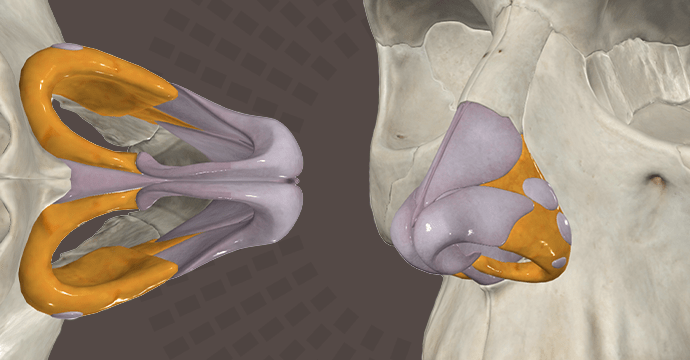

Take your understanding of human anatomy to the next level. Our comprehensive resources combine detailed information and stunning illustrations!

Enhance your studies for a truly dynamic learning experience. Explore interactive anatomy models from Complete Anatomy. Start mastering anatomy today with our free anatomy flashcards designed for quick review on the go.